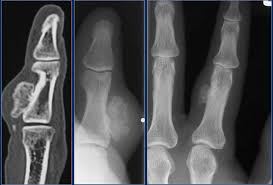

What Does Bone Cancer Of The Foot Look Like / Chondrosarcoma Of The Distal Phalanx Of The Right Great Toe Report Of A Rare Malignancy And Review Of Literature Mondal Sk J Can Res Ther / This is the most common type, but not the most dangerous type of skin cancer of the foot, toe and ankle.

A skull consists of the frontal, temporal, parietal and occipital bones. This type of cancer usually does not spread deep, except when allowed to progress for a. The pain can sometimes be wrongly mistaken for arthritis in adults and growing pains in children and teenagers. Although rare, bone tumors can occur in the foot and ankle. Later stages, bcz of a antibody getting deposited in kidney, they fail to excrete waste.now we will have kidney failure symptoms like swelling of legs,puffiness of face, altered urine output and.